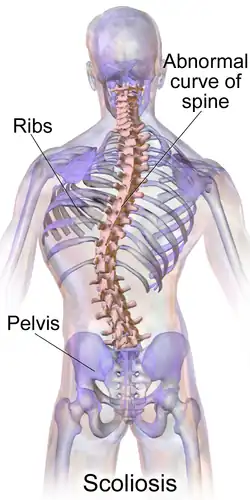

Scoliosis

Scoliosis (pl.: scolioses) spine has an irregular curve[2] in the coronal plane. The curve is usually S- or C-shaped over three dimensions.[2][7] In some, the degree of curve is stable, while in others, it increases over time.[3] Mild scoliosis does not typically cause problems, but more severe cases can affect breathing and movement.[3][8] Pain is usually present in adults, and can worsen with age.[9] As the condition progresses, it may alter a person's life, and hence can also be considered a disability.[10] It can be compared to kyphosis and lordosis, other abnormal curvatures of the spine which are in the sagittal plane (front-back) rather than the coronal (left-right).

Definition

Scoliosis is defined as a three-dimensional deviation in the axis of a person's spine.[46][7] Most instances, including the Scoliosis Research Society, define scoliosis as a Cobb angle of more than 10° to the right or left as the examiner faces the person, i.e. in the coronal plane.[86]